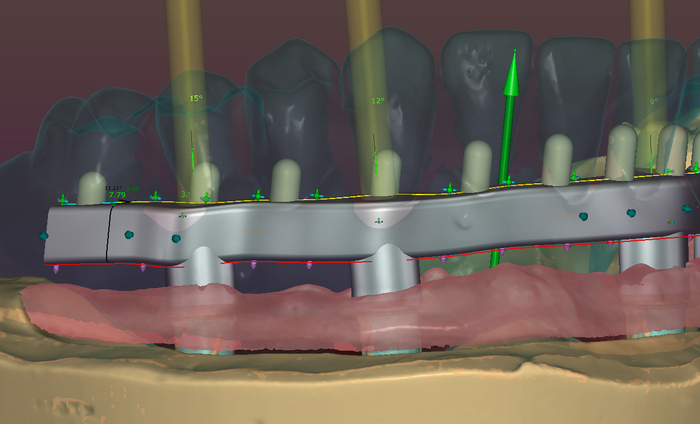

Балку получил из фрезерного центра, теперь надо её проверить на качество "посадки" на аналоги имплантов и в случае если будет баланс припассовать.

Титановый каркас "сидит" как надо не качается и не балансирует; не только на лабораторной модели, но и в полости рта — можно продолжать.

С восковой постановки зубов снимается "ключ" с помощью которого зубы переносятся на каркас.

Далее проверяю если не нарушилось положение зубов при переносе, моделирую форму десны будущих протезов, снимаю при помощи технического силикона формы в которые заливается пластмасса.